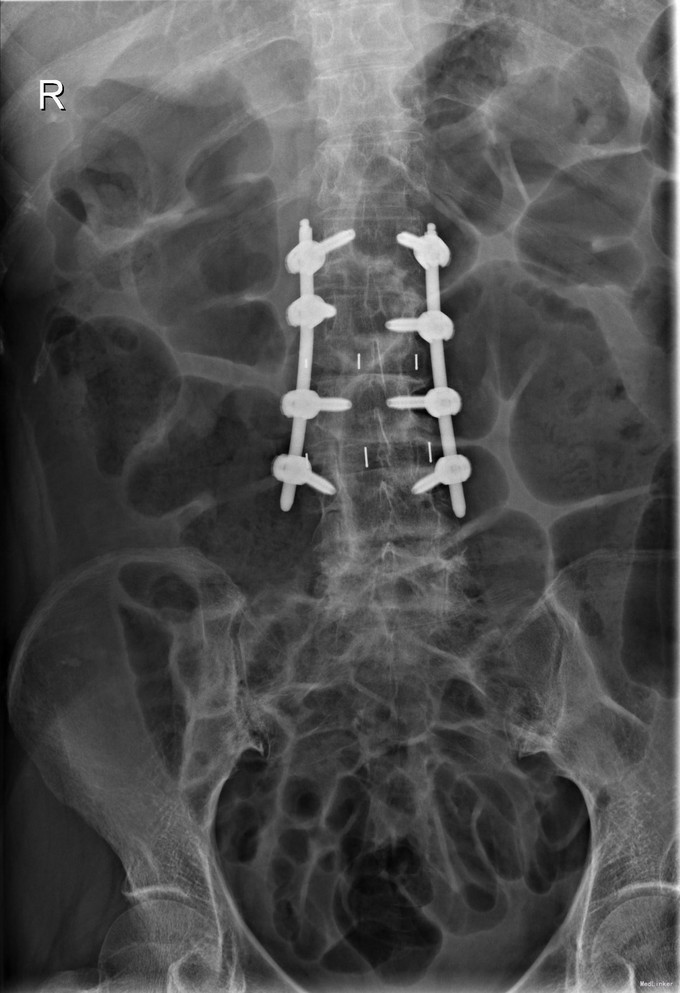

查体:脊柱无明显侧弯,腰背部无压痛,双下肢麻木酸痛,可牵连至脚跟。肌力肌张力可。腰部活动可,前屈后伸时感酸痛,无力。左侧直腿抬高试验阳性。 辅助检查:X线平片:腰椎侧弯前屈,L3椎体轻度滑脱,各椎间隙狭窄,腰椎退行性改变。 MRI:L4-5,L5-S1椎间盘膨出,L2-3,L3-4,L5-S1椎间隙狭窄,S2-3水平骶管内蛛网膜囊肿,腰椎序列不稳定,生理曲度局部后凸。

诊断:1 脊柱侧弯 伴不稳 2椎管狭窄 治疗: 前期微创腰椎侧路融合手术+后期 微创后路经皮内固定

随访:术后1月,患者腰部及腿部酸痛改善,步行良好。